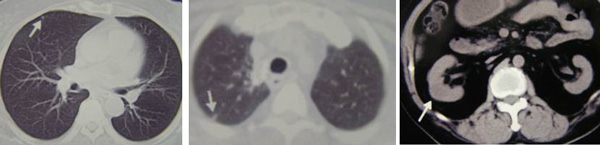

As I have said, we are indeed amazed that Sujo did not have any problem with respect to his lung cancer! Look again at the condition of his lungs when he first came to see us. He started to take the herbs and was well. Since then he did not have any problems with his lungs. Now, he has problems with his mobility!

Lung-compo-2Lung-compo-1